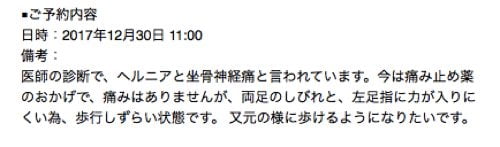

ネットでご予約を頂いた際に書いて下さったご要望はこんな感じです。

医師の診断で、ヘルニアと坐骨神経痛と言われています。今は痛み止め薬のおかげで、痛みはありませんが、両足のしびれと、左足指に力が入りにくい為、歩行しずらい状態です。 又元の様に歩けるようになりたいです。

現在のお身体の状態

現在の状況を書いて頂くと

両足の痺れ

腰は一定以上に動かすと痛み

足の指に力が入らない為 歩行がしづらい

そんな状態です。